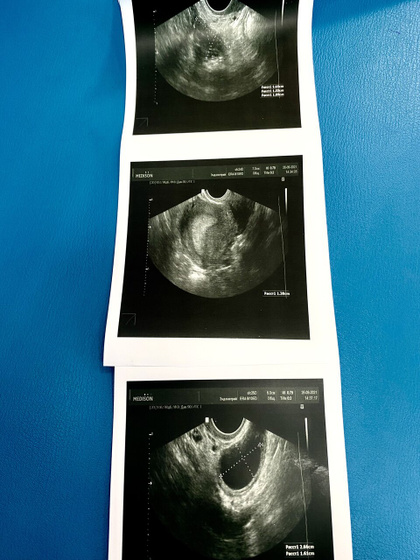

Больше в женскую консультацию я не ногой на УЗИ? Мысленно готовлюсь к двойне, после слов врача?? Результаты узи меня просто шокировали, как никогда, давно у меня не было таких показателей, сегодня 24 день цикла:

Эндометрий за два дня подрос и стал 14 мм, в левом яичнике два жёлтых тела 26 мм и 29 мм с хорошим кровотоком! Посоветовали сдать ХГЧ, после 28 дня цикла ? РАЗРЫВ КИСТЫ ОПРОВЕРГЛИ НА 100 % и это главное ?

В итоге этого слава богу ничего нет ) но зато есть два прекрасных жёлтых тела и эндометрий пышный хороший шанс на удачный исход сказали )